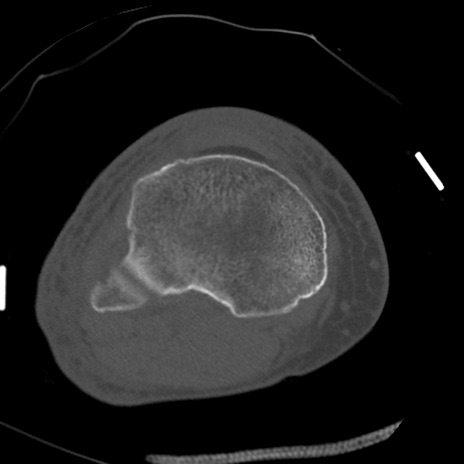

症例28 右膝関節CT(横断像)

右膝関節CT